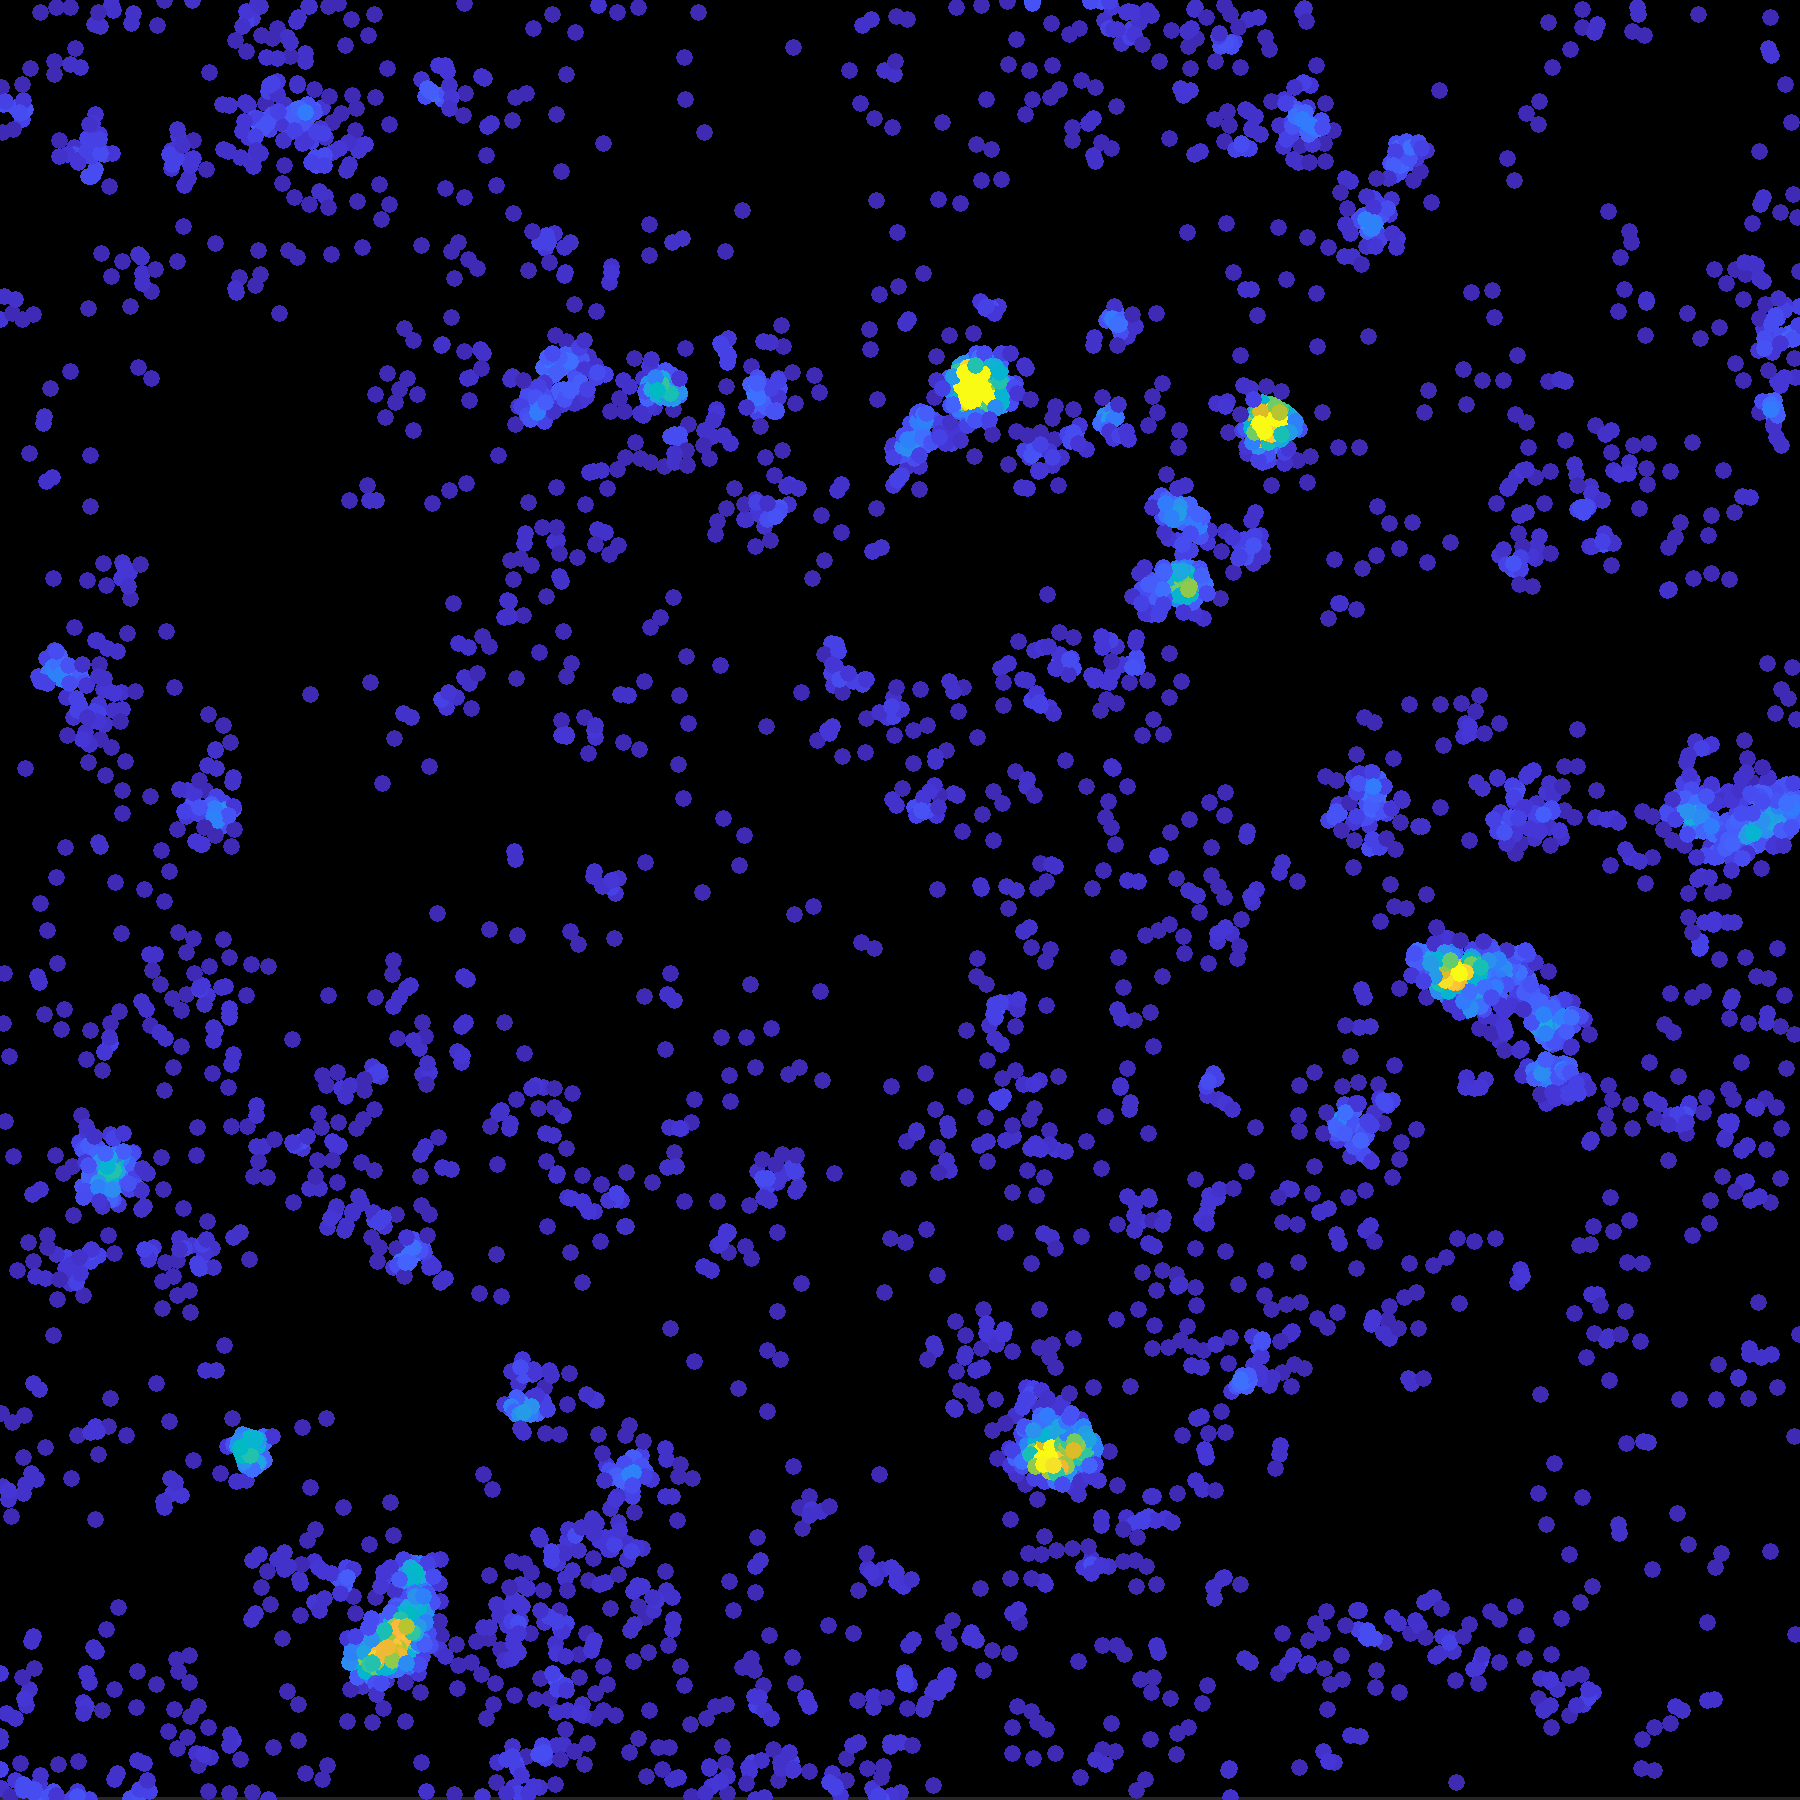

Representative diffraction-limited image of a neuroblastoma cell expressing Tau-mEos3.2 molecules acquired in the green channel before single-molecule imaging. Credit: Dr Pranesh Padmanabhan / Queensland Brain Institute

“Firstly, we found that Tau localised to the plasma membrane and displayed highly heterogeneous behaviour in space and time.

“But a more intriguing finding was that these proteins started to form what is called a hot spot, within which Tau molecules are highly immobilised.